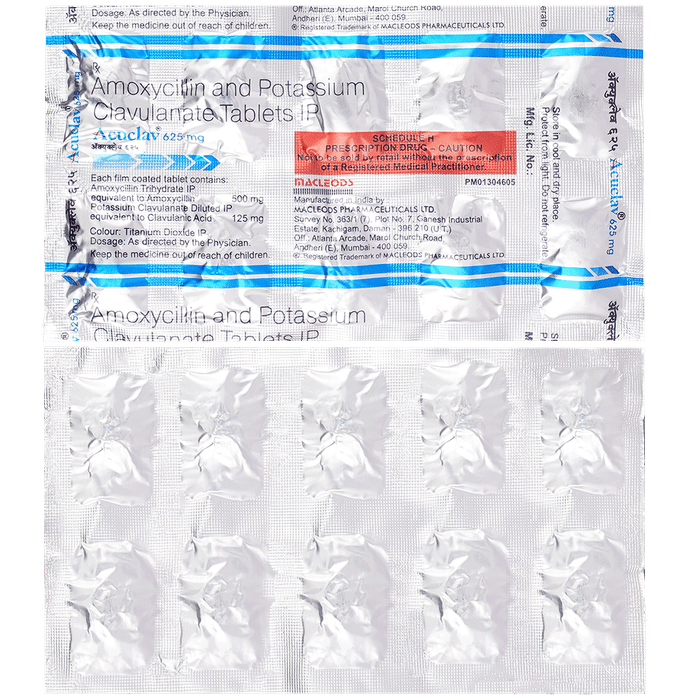

Prescription Required:Macleods Pharmaceuticals Pvt Ltd:<medicine_type>:

Amoxycillin (500mg) + Clavulanic Acid (125mg):<packagingdetail>:Strip:

10:<productform>::Store below 30°C:

Macleods Pharmaceuticals Pvt Ltd | Atlanta Arcade, Marol Church Road, Andheri (East), Mumbai – 400059, INDIA.::